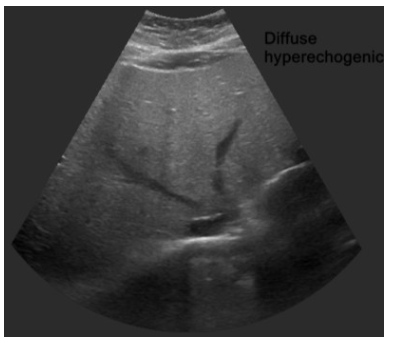

Fatty liver 초음파 소견

간초음파 사진의 diffusely increased echogenicity는 지방간 소견입니다.정상 hepatic vein의 wall은 liver parenchyme보다 hyperechoic하지만 사진의 hepatic vein wall은 isoechoic하며 parenchyme의 echogenicity가 증가되어 있음을 알 수 있습니다.

① 정상 hepatic vein의 wall은 liver parenchyme보다 hyperechoic하지만 지방간에서는 isoechoic합니다 (아래 첫 번째 사진과 세 번째 사진 비교)